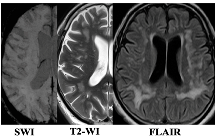

| F3 MRI Type 1 | F3 MRI Type 2 |

![]() | ![]() |

| WMH: more pronounced in the periventricular and deep regions of the cerebral hemispheres, subcortical structures, external capsule, brainstem, and cerebellum | WMH: periventricular—in the posterior cerebral hemispheres, deep—in the frontal and parietal lobes |

| Lacunes: multiple in subcortical structures and cerebral white matter | Lacunes: single in the white matter of the cerebral hemispheres |

| CMB: juxtacortical CMHs in all regions of the cerebral hemispheres, in subcortical structures | CMB: single juxtacortical CMHs in the white matter of the temporal and parietal lobes |

| Cerebral atrophy: more pronounced | Cerebral atrophy: less pronounced |

| Enlarged PVS: pronounced in subcortical structures | Enlarged PVS: extended |

| Cognitive impairment: more pronounced (MCI and dementia) | Cognitive impairment: less pronounced (SubCI and MCI) |

| Gait disorders: more pronounced | Gait disorders: less pronounced |

| Reduced VEGF-A | Increased TNF-α |